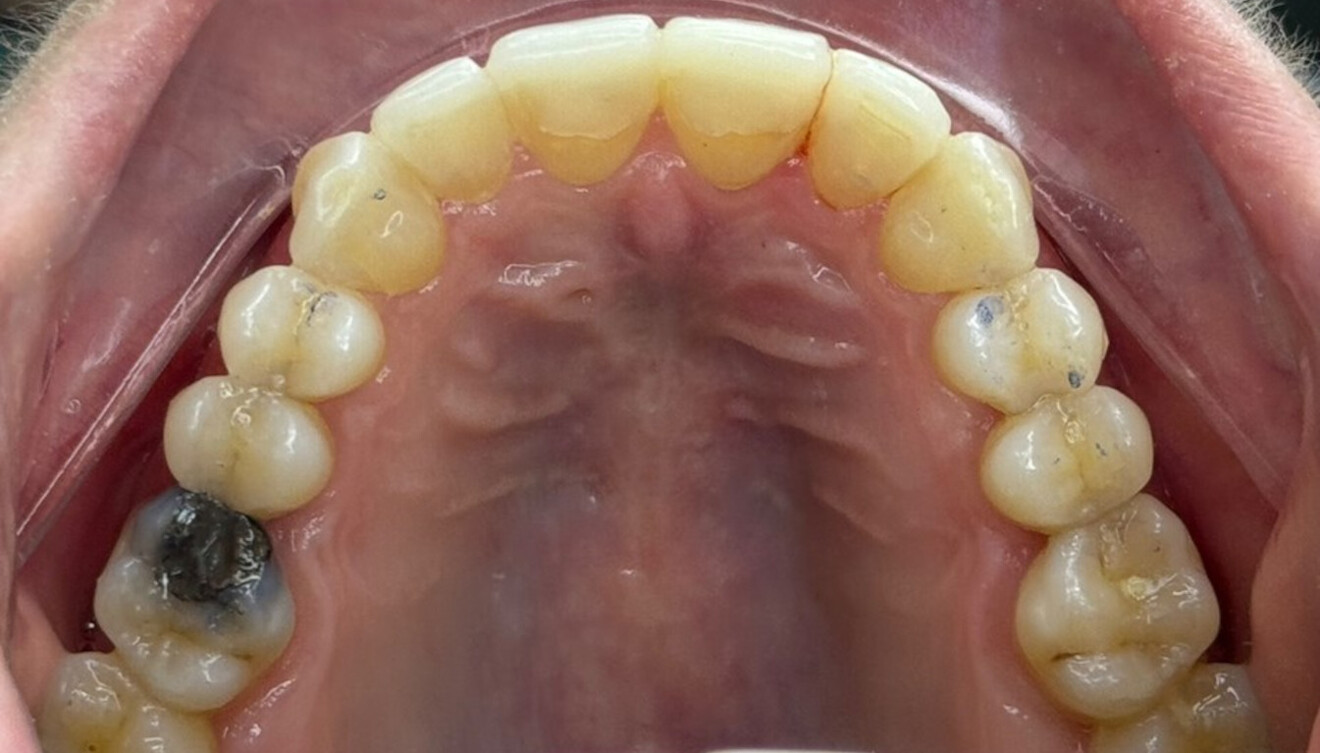

Fig. 4: Intra-oral pre-treatment photograph.

Figs. 6a–e: Intra-oral post-treatment photographs.